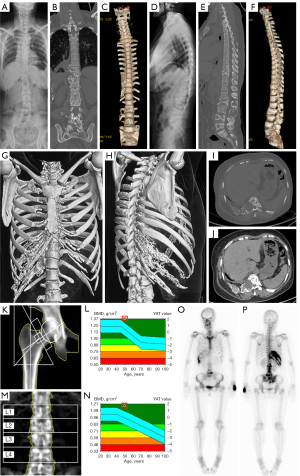

A previously healthy 50-year-old woman presented to the bone metabolism clinic of endocrinology at our medical center with moderate lower back pain and occasional numb pain in the right ribs. These symptoms had lasted for approximately 7 years without obvious limitation to her body flexion or movements. As a mother of two healthy teenage girls, she had no special medical, family, or psycho-social history of diseases. Not long ago, she had just visited a primary clinic, where radiographs showed massive osteolysis at multiple lumbar vertebrae and the right ribs (Figure 2A-2J). By physical examination to her body, mild percussion pain was detected at the T10-L3 level, but not in the right rib cage. Her body temperature, heart rate, and blood pressure were normal, and no coffee spots were observed. The thyroid gland was not enlarged, the thorax was not deformed or painful, the lungs were normal, the abdomen was normal on palpation, and no lower extremities were swollen. No deformity or pressure pain was observed in the spine or extremities. This patient was suspected of having GSD and was prescribed blood tests, urine tests, further radiographs, emission computed tomography (ECT), ultrasonography, and tuberculosis screening. The results of routine blood tests, blood sedimentation, blood lipids, liver function, kidney function, parathyroid function, thyroid function, vitamin D, blood tumor markers, calcium, phosphorus, magnesium, urine routine, 24 h urine calcium, 24 h urine phosphorus, blood immunoelectrophoresis, and urine immunoelectrophoresis were all normal. Abdominal ultrasonography results were also normal, as was bone density in the uninvolved area (Figure 2K-2N). ECT of whole-body bone imaging showed abnormally high uptake in the T10 and T11 vertebrae, right 8th–11th posterior ribs, lumbosacral vertebrae below L2, and bilateral sacroiliac joints (Figure 2O,2P). Additionally, ECT of the upper limb lymphography was normal. The patient was then referred to the orthopedic clinic for diagnostic bone biopsy to rule out bone related malignancies and to evaluate the indications for vertebral strengthening procedures such as percutaneous vertebroplasty (PVP). Upon admission to orthopedic ward, percutaneous puncture biopsies of T10 and T11 vertebrae were performed successfully under local anesthesia (Figure 3A-3E). The pathology results reported vertebral bone tissue and hyperplastic fibrous tissue without detectable malignancy to the bone (Figure 3F). The IHC staining was also performed and showed SMA (scattered +), desmin (−), CD34 (scattered +), S-100 (−), Ki-67 (bone marrow tissue index 80%), AE1/AE3 (−), CD15 (+), CD3 (+), CD20 (+), CD138 (+), and MPO (+). No PVP or other invasive procedures were recommended, considering the scattered yet symptomless osteolysis in the bones. This patient returned to the endocrinology clinic and was confirmed with GSD diagnosis. She was then prescribed a regimen of 5 mg of bisphosphonates per year, 0.25 µg of osteotriol every 2 days, 600 mg of calcium and 125 U of vitamin D per day, which was recommended until complete recession of disease. Allopathic treatment with Tylenol was also prescribed for occasional pain, and a regular follow-up plan was scheduled every 3 months. She returned to the outpatient clinic with relief of lower back pain, mild pleural effusion, and no onset of new symptoms or signs of newly onset of osteolysis after 3 months of treatment (Figure 4A). The patient was advised to visit the respiratory medicine clinic for monitoring of minor pleural effusion and was referred to the interventional center of radiology for undecided indications of pleural biopsy. Considering that there was no particularly safe puncture access according to the CT imaging, and that minor pleural effusion did not cause significant chest tightness, the radiologist recommended re-evaluation by imaging within 3 months. The patient continued with the original regimen and returned 3 months later with almost no back pain. Repeated imaging revealed reduced pleural effusion and static osteolysis on the 12th months revisit (Figure 4B) and 18th month revisit (Figure 4C,4D). During the entire diagnostic and therapeutic process, this patient fully cooperated with the diagnostic and therapeutic procedures. She gladly adhered to the regimens without adverse or unanticipated events. With the current treatment plan, the patient’s condition gradually stabilized, and remission was gradually achieved. Until the eighteenth months since the first visit, the patient had continued with her normal life. The medical expenses are affordable with basic citizen insurance, and her mind is relieved and healthy.